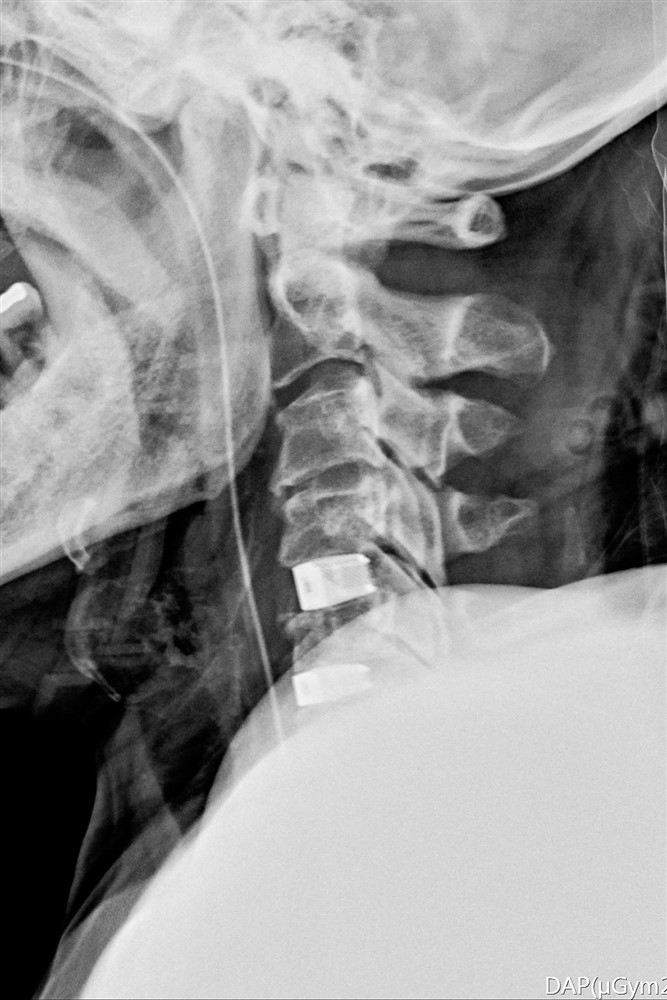

李建輝醫師以脊椎內固及融合微創手術,清除突出的椎間盤後放入填充物,並用支架固定頸椎。圖/花蓮慈院提供

李建輝主任表示,當時在急診看到徐女士,先說自己四肢癱軟無力,發現她一直在用肚子呼吸,無法自然擴胸呼吸,令他警覺有可能是頸椎神經受損,因為控制橫膈的神經就在頸椎附近,檢查後確認是第四到六節的神經被壓迫,且能清楚看到骨刺壓迫已造成脊髓損傷,有癱瘓風險,需儘快手術清除及重建,提高恢復的可能性,隨即在隔天進行手術,清除突出的椎間盤後放入填充物,並用支架固定頸椎。